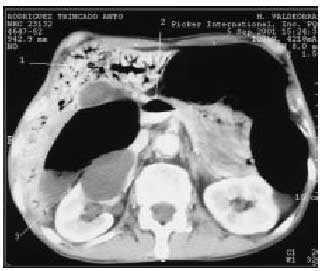

Se realiza tomografía computarizada abdominal urgente sin y con contraste intravenoso (fig. 2), en la que se aprecia la existencia de gas en vasos portales intrahepáticos (flecha 1), vena porta y vasos mesentéricos, con nivel gas-contraste en vena porta y vena mesentérica superior (flecha 2). Neumatosis en pared intestinal, sobre todo en colon ascendente (flecha 3).

Fig. 2.